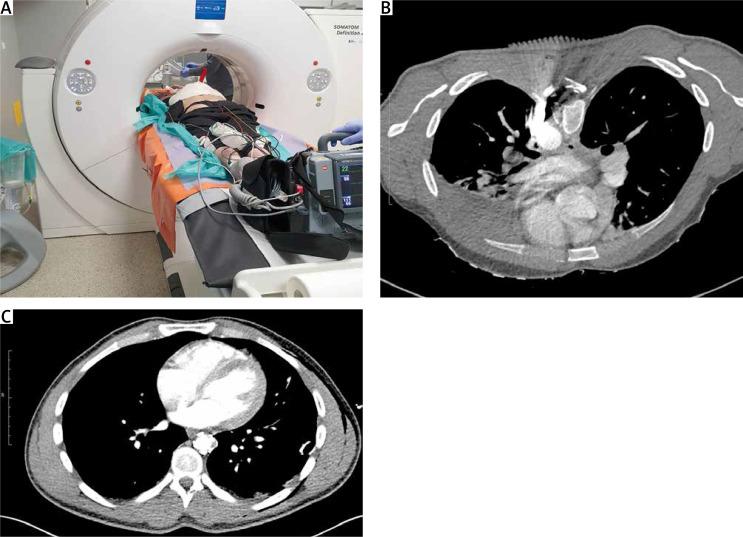

Hybrid treatment of penetrating aortic trauma.

https://cdn.ncbi.nlm.nih.gov/pmc/blobs/3acb/11059023/20f2e4b7a886/KITP-21-53835-g001.jpg